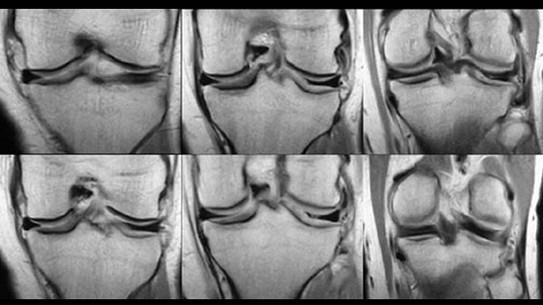

请根据所提供的图像,选择最佳选项是 ( )A、半月板损伤B、半月板囊变C、桶状半月板D、半月板黏液样变E、盘状半月板

问题 请根据所提供的图像,选择最佳选项是 ( )

选项 A、半月板损伤 B、半月板囊变 C、桶状半月板 D、半月板黏液样变 E、盘状半月板

答案 E